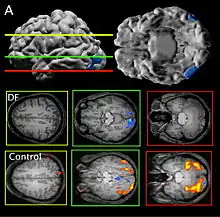

Patient DF's brain damage resulted from hypoxia due to carbon monoxide poisoning.[2] The lateral occipital cortex (LOC) in her brain is severely damaged and shows no activation presented with line drawings of common objects where healthy people usually do. Moreover, there is a reduction of white matter connections between LOC and other areas.[3] There is also some shrinkage in the intraparietal sulcus, often implicated in the dorsal stream for visuomotor control. The fusiform face area is intact. This would suggest the problem in DF's perception is disconnectivity between higher and lower order functioning.[2]

Recent MRIs have shown many enlarged sulci, like the intraparietal sulcus, parieto-occipital sulcus, and left calcarine sulcus, indicating atrophy.[2] Her visual field remains intact up to 30 degrees.[1]

DF does not benefit from haptic feedback—allowing her to pick up an object does not let her better estimate its width next time.[4] DF also does not use visual information about her grasp: when she can only see her grip in a distorted mirror, her performance does not change.[2] Consistent with all of this, brain imaging has shown no response to line drawings in her ventral stream. Furthermore, according to fMRI studies, the intraparietal sulcus showed preference for grasping motions over reaching motions—actually grabbing an object, in both DF and control patients, activates the intraparietal sulcus more than reaching.[2]